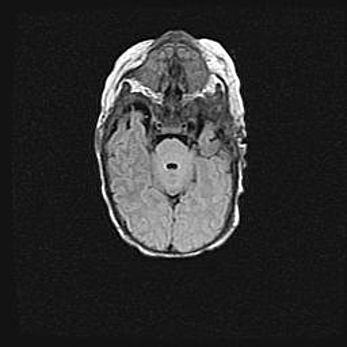

Подострая гематома правой гемисферы мозжечка.

Наружная гидроцефалия.

Возраст: 15 дней

Вес: 3100 г

Пол: женский

Окружность головы: 37 см

Срок гестации: 35-36 недель

При открытой наружной форме гидроцефалии у новорожденных расширяются и переполняются субарахноидные пространства.

Кровоизлияния в мозжечок имеют две клинико-анатомические формы: полушарные гематомы и кровоизлияния в червь.

К появлению этой патологии может привести: повреждения головного мозга, возникающие в результате асфиксии и гипоксии плода при беременности, или травмы во время родов. Редко гематома мозжечка может быть результатом первичной коагулопатии и сосудистой мальформации, диссеминированном внутрисосудистом свертывании, изоиммунной тромбоцитопении.